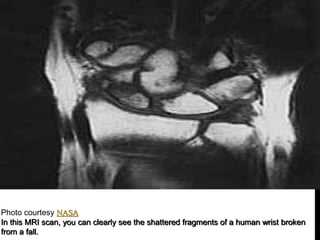

Photo courtesy NASA

An MRI scanner. See more MRI pictures and images .

In this MRI scan, you can clearly see the shattered fragments of a human wrist broken

from a fall.

Photo courtesy NASA AnMRI scanner. See more MRI pictures and images .

• 50.

Photo courtesy NASA Inthis MRI scan, you can clearly see the shattered fragments of a human wrist broken from a fall.